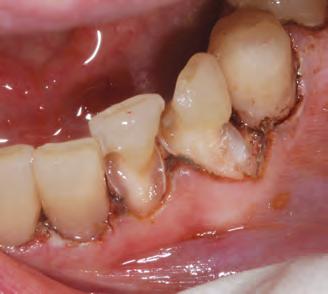

1. Subgingival preparation with bleeding. BLEEDING HEMOSTASIS

2. Scrub Astringedent™ X hemostatic firmly against bleeding tissues with Metal DentoInfusor™ tip.

CLEANING/TESTINGDISPLACEMENT

3. Firm air/water spray removes residual

and tests tissue for quality, profound hemostasis.

Remove

4. Soak Ultrapak™ knitted cord in Astringedent™ X hemostatic, pack, and leave for 5 minutes.